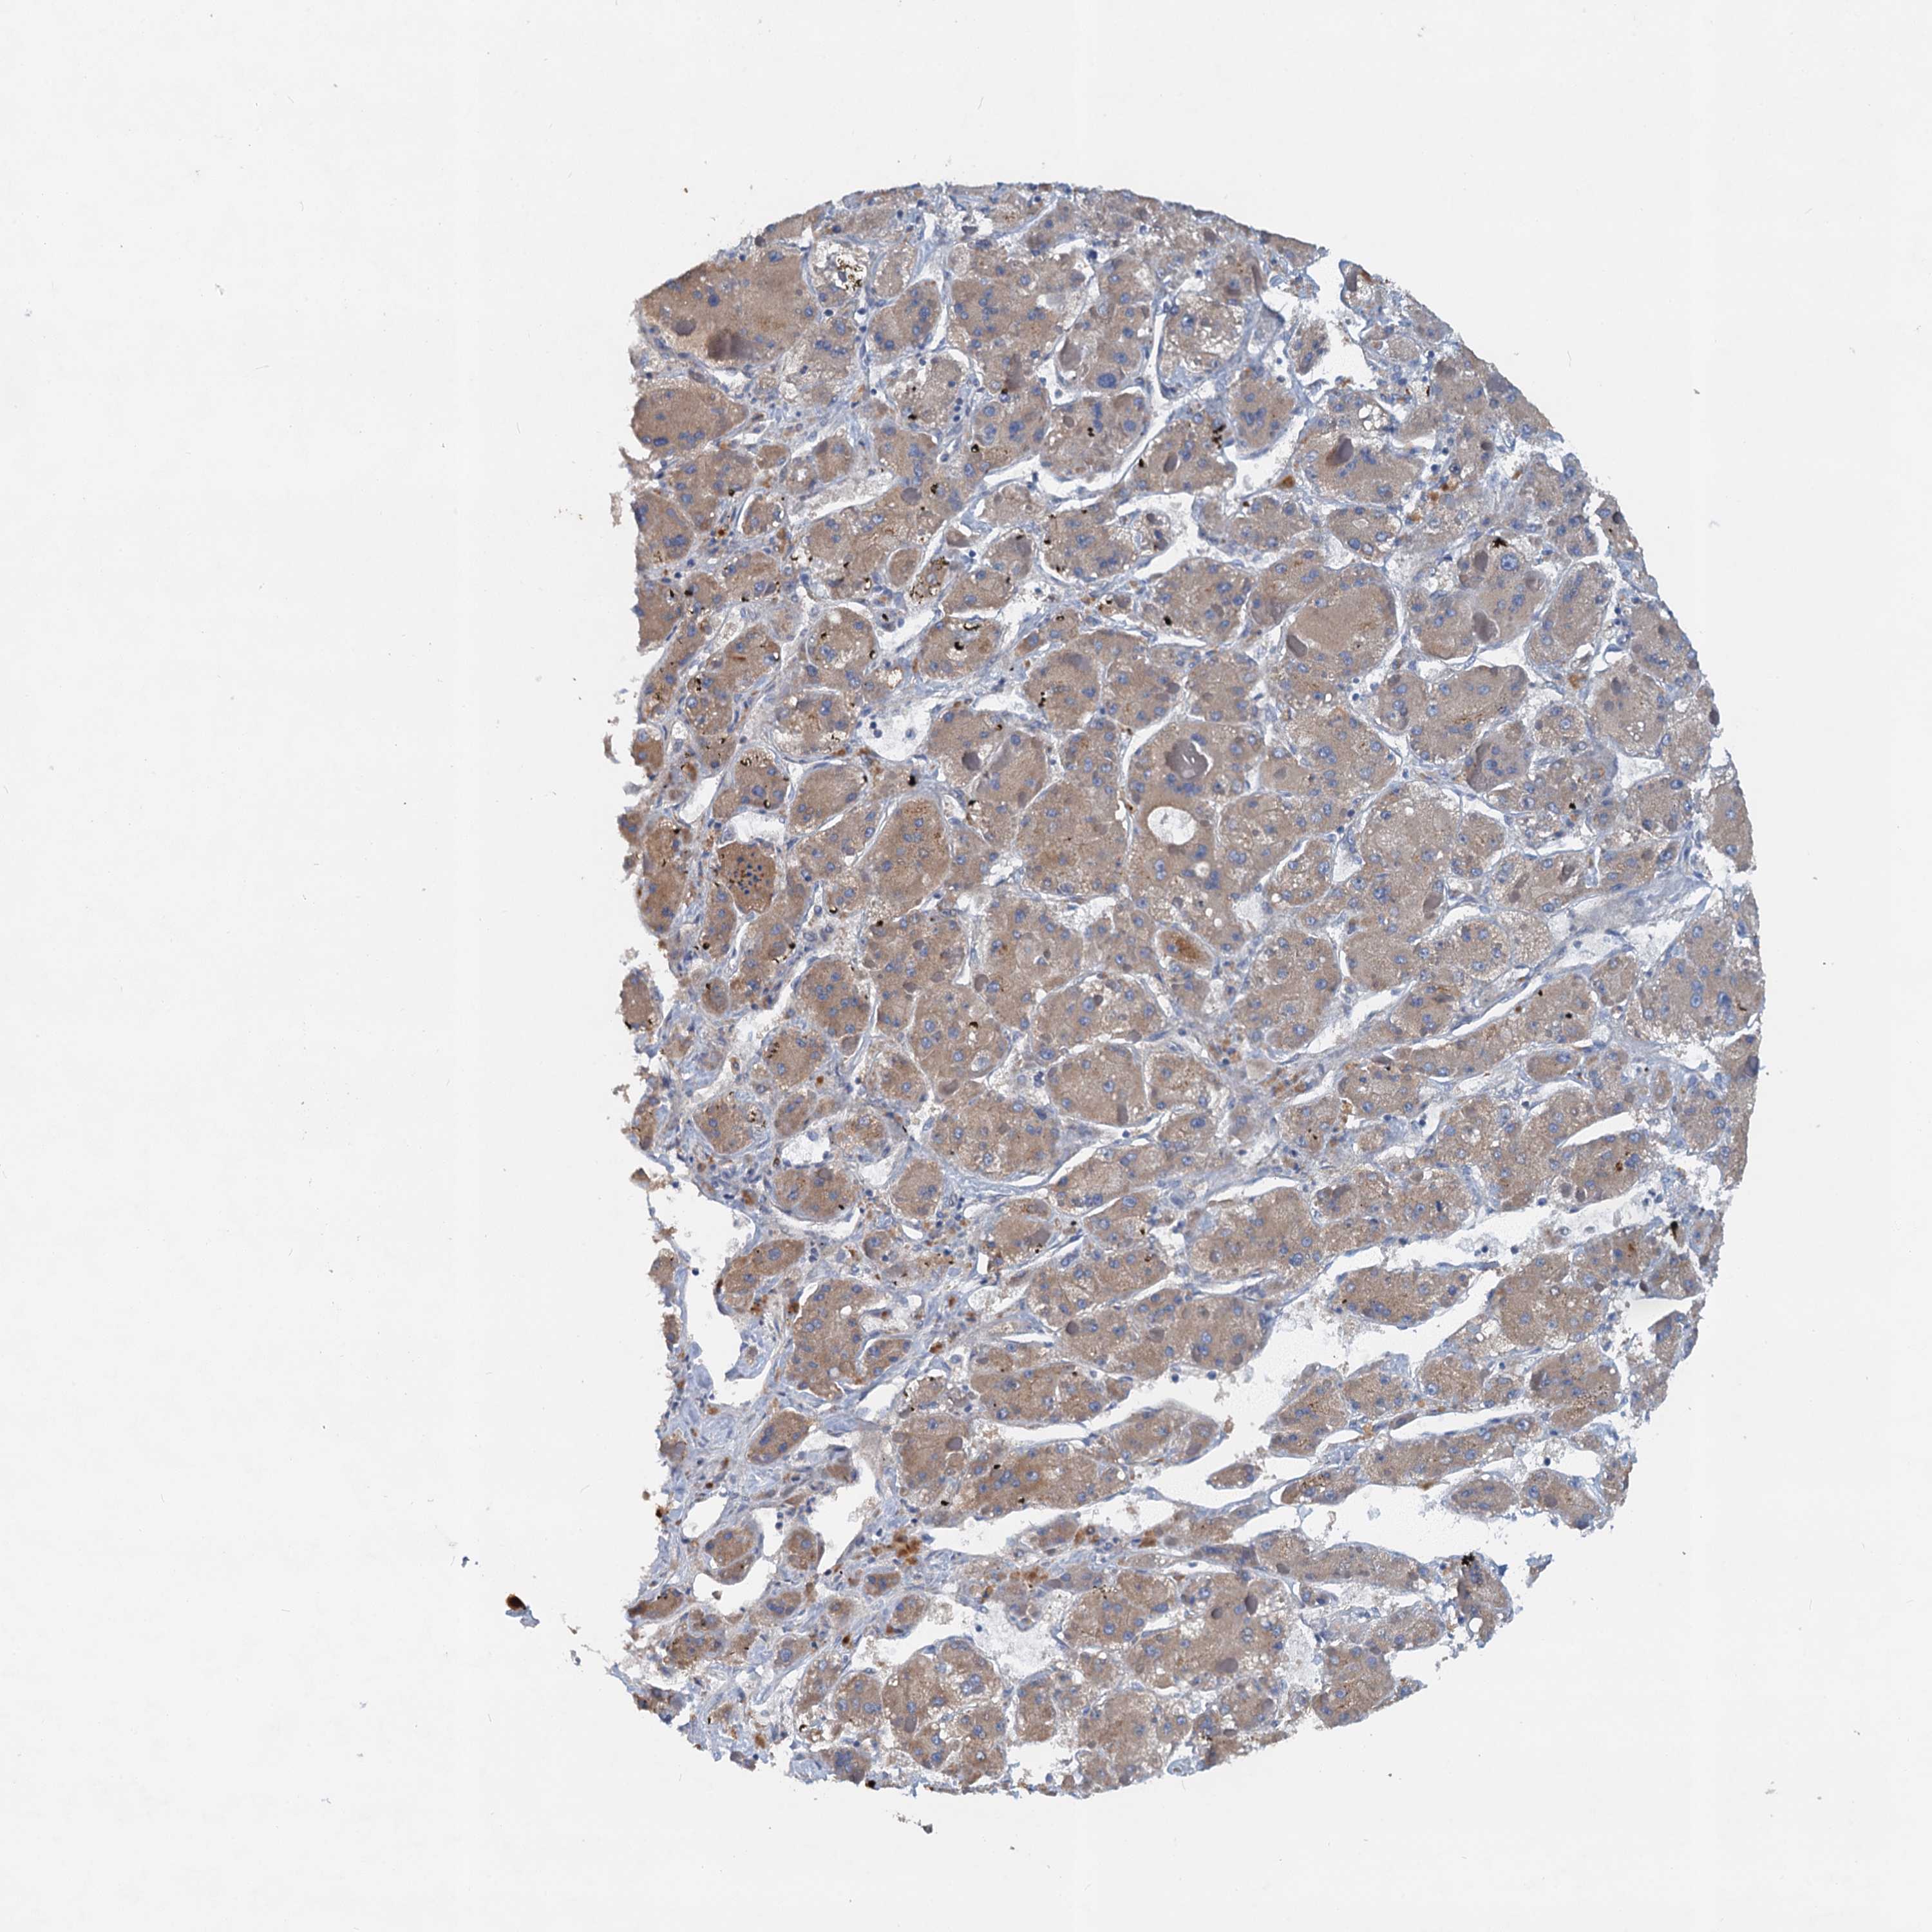

LIVER CANCER - Protein expressioni

A mouse-over function shows sample information and annotation data. Click on an image to view it in a full screen mode. Samples can be filtered based on level of antibody staining by selecting one or several of the following categories: high, medium, low and not detected. The assay and annotation is described here.

Note that samples used for immunohistochemistry by the Human Protein Atlas do not correspond to samples in the TCGA dataset.

Antibody stainingi

Antibody staining in the annotated cell types in the current human tissue is reported as not detected, low, medium, or high, based on conventional immunohistochemistry profiling in selected tissues. This score is based on the combination of the staining intensity and fraction of stained cells.

Each image is clickable and will lead to virtual microscopy that enables deeper exploration of all samples and also displays staining intensity scores, fraction scores and subcellular localization as well as patient and tissue information for each sample.

Antibody HPA039730

Antibody HPA040385

Staining

High

Medium

Low

Not detected

Intensity

Strong

Moderate

Weak

Negative

Quantity

>75%

75%-25%

<25%

None

Location

Nuclear

Cytoplasmic/membranous

Cytoplasmic/membranous,nuclear

Cholangiocarcinoma

Carcinoma, Hepatocellular, NOS